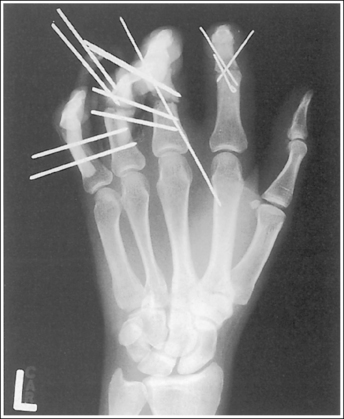

See Figure 4-27 and Box 4-10.

The second through fifth digits are separated, demonstrating little superimposition of the proximal bony or soft tissue structures. The thumb is demonstrated without superimposition of the other digits. Its position may vary from a PA projection to a slight PA oblique projection.

• For a lateral hand projection, place the medial hand surface resting against the IR; then fan or spread the fingers as far apart as possible without superimposing the thumb. The fingers are fanned most effectively by drawing the second and third fingers anteriorly and the fourth and fifth fingers posteriorly. The amount of finger separation obtained will depend on the patient's mobility (Figure 4-28). Immobilization devices are available to help maintain proper positioning. When the fingers are fanned, they can be individually studied. If the fingers are not adequately separated, they superimpose one another on the image (see Images 26 and 28).

The second through fifth metacarpals are superimposed.

• Superimpose the second through fifth metacarpals by palpating the patient's knuckles and placing them directly on top of one another.

• Verifying a lateral hand projection. On a lateral hand projection, a true lateral wrist position, represented by superimposition of the ulna and radius, is not always accomplished when the metacarpal midshafts are superimposed. Instead, the ulna is demonstrated slightly posterior to the radius. Because of this variation, a true lateral projection of the hand should be determined by judging the degree of superimposition of the second through fifth metacarpal midshafts and not the degree of ulnar and radial superimposition. If the metacarpal midshafts are not superimposed and the fifth metacarpal is demonstrated anterior to the second through fourth metacarpals, the hand was slightly externally rotated or supinated (see Image 26). The fifth metacarpal can be identified by its length; it is the shortest of the second through fifth metacarpals. If the metacarpal midshafts are not superimposed and the second metacarpal is demonstrated anterior to the third through fifth metacarpals, the hand was slightly internally rotated or pronated (see Images 27 and 28). The second metacarpal can also be identified by its length; it is the longest.

The IP joints are open, and the phalanges are not foreshortened.

The MP joints are at the center of the exposure field. The distal, middle, and proximal phalanges, the metacarpals, the carpals, and approximately 1 inch (2.5 cm) of the distal radius and ulna are included within the collimated field.

• Center a perpendicular central ray to the second MP joint to place it in the center of the collimated light field. Once the central ray is centered, open the longitudinal collimation to include the distal phalanges and the distal forearm. Transversely collimate to within 0.5 inch (1.25 cm) of the first and fifth finger's skin line.